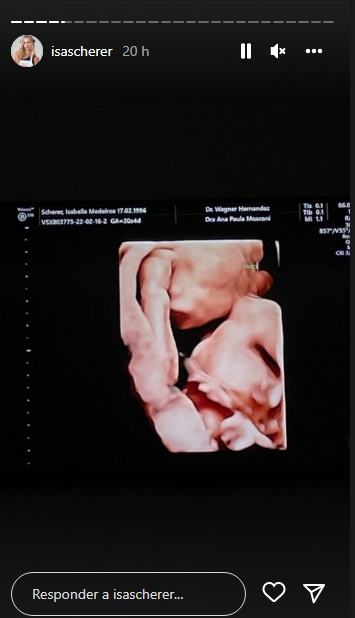

A atriz, que foi campeã da ultima edição do Masterchef Brasil, decidiu compartilhar o momento mais que especial, a loira surgiu já pronta para realizar o exame e revelou estar acompanhada da avó. Logo em seguida Isa publicou fotos do ultrassom dos bebês e explicou que os dois estão se desenvolvendo bem e estão maiores que o esperado para uma gestação gemelar.

“Eles estão enormes. Eu tô de 20 semanas, mas eles já estão com tamanho de 21 semanas e quatro dias. A médica falou que eles estão com tamanho de bebê de gestação única”, explicou a filha do ex-nadador Fernando Scherer na ultima nesta sexta-feira (6).

Confira fotos abaixo: